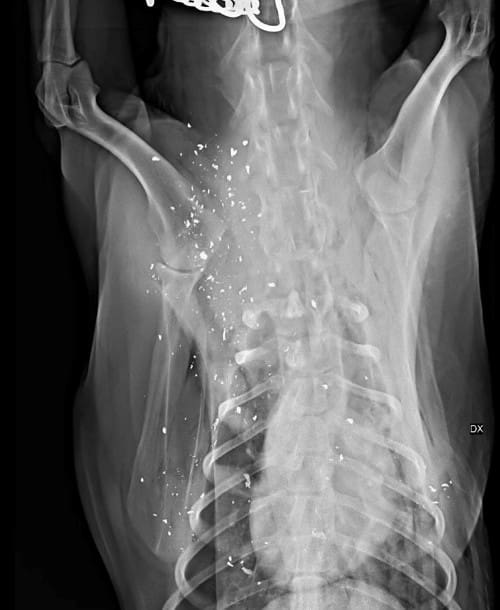

Foto: Privat Röntgen visar att den skjutna hunden har 300 blyfragment i kroppen efter att kulan gick genom kevlarvästen. Björn hoppas att de med tiden ska kapplas in.

Det var framför allt efterspelet som väckte känslor. Skottet, som gick genom en kevlarväst, förstörde en stor del av muskelmassan för Lotus, en blandning av laika och jämte.